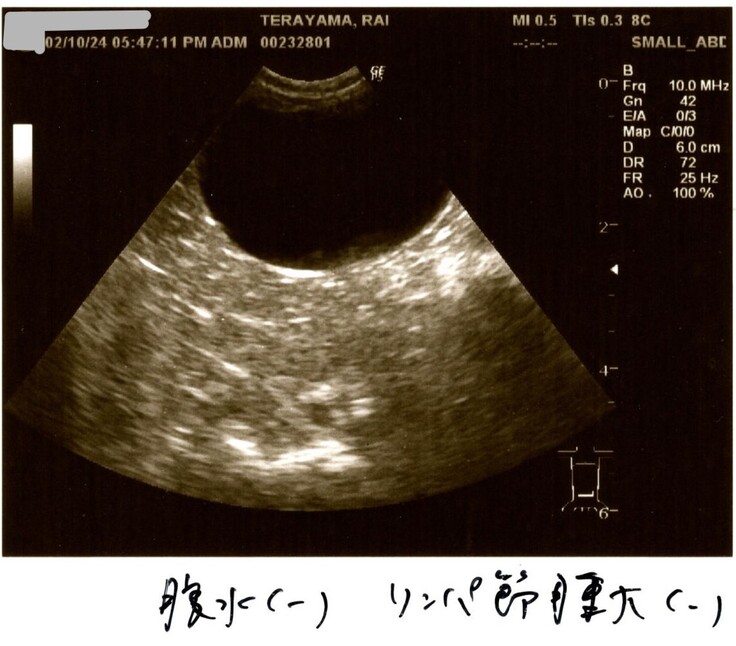

2/10検査結果

2/10はらいくんの2度目の検査結果を聞きました。

何と検査結果は全て改善していました!

血液検査も貧血や黄疸は改善!

油断はもちろんできないけれど、基準値に近づいているものもあり✨

炎症マーカー(血液検査の炎症反応)

改善はしてきていますが、まだまだ高いのでらいくんは辛かったのだと思います。